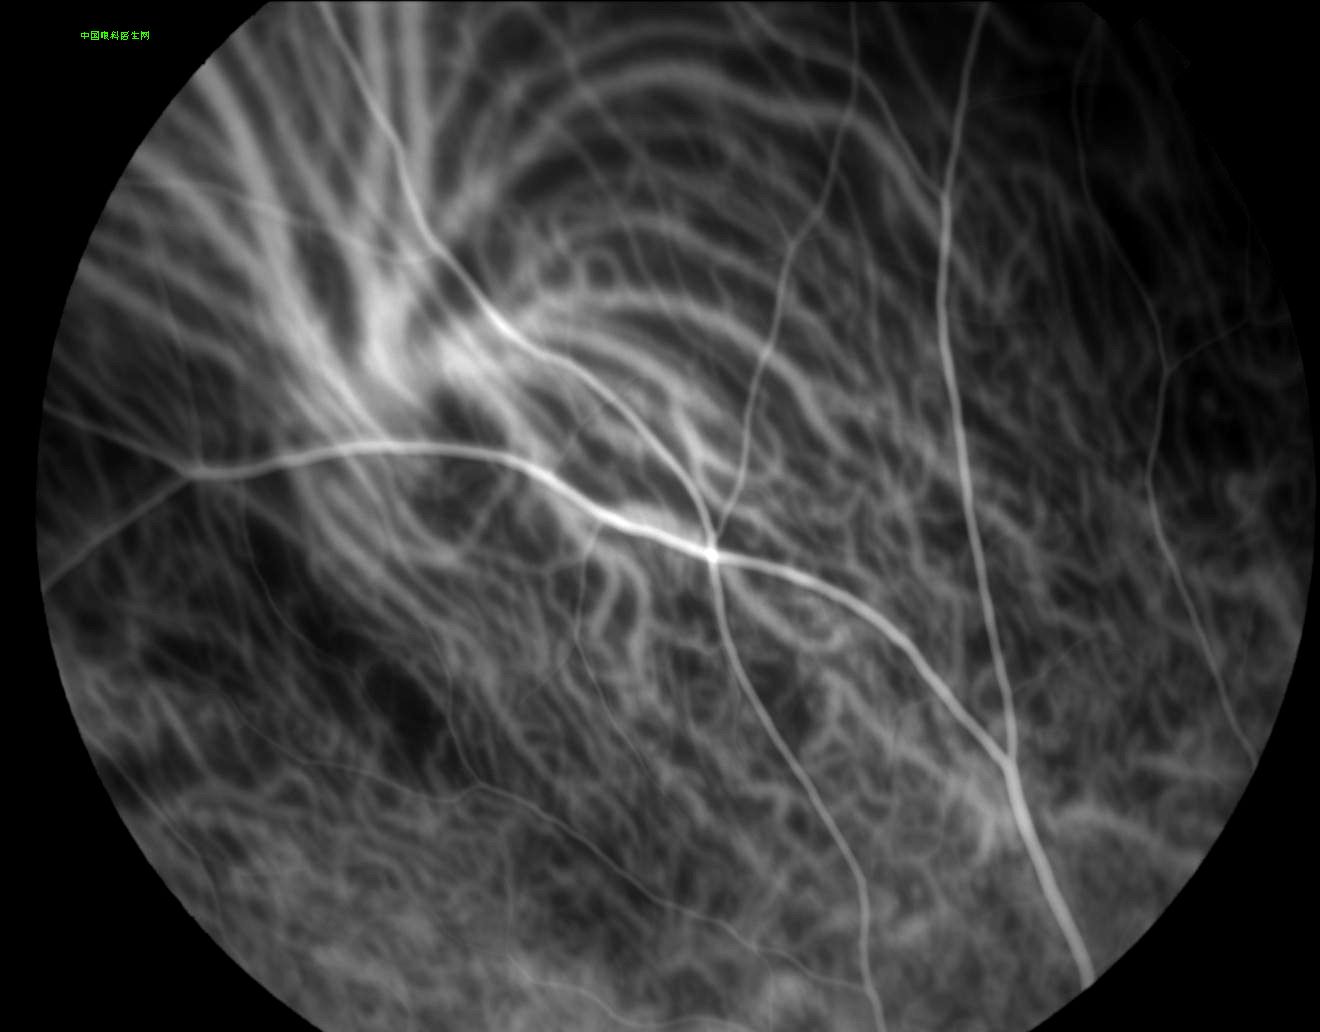

涡状静脉

http://www.cnophol.com 2008-10-6 14:18:56 中华眼科在线

(来源:中国眼科医生网)(责编:zhanghui)